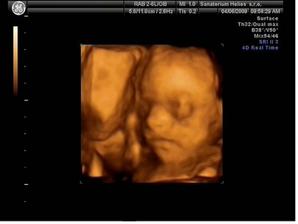

Naše milovaná Lucinka

Lucinka se narodila 9.7 2009 vážila 2930g a měřila 47cm. Je to náš maličkej drobeček 🙂)